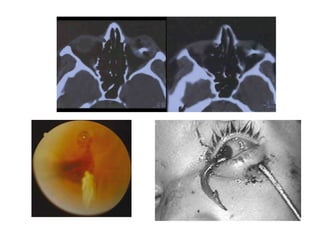

Trauma Ocular Abierto Cuerpo Extraño Intraocular Los CEIO ocupan entre un 15 y 25 % de los traumas oculares a globo abierto.  Aumento de riesgo de endoftalmitis, hemorragia vítrea, rotura retiniana posterior e incarceración retiniana.  La localización de la penetración ocular puede variar dependiendo del mecanismo del trauma. Remitir oftalmólogo Hospitalizar: ATB amplio espectro

Trauma Ocular Abierto Dx:  agudeza visual, biomicroscopía, oftalmoscopía directa e indirecta (precisar el trayecto del cuerpo extraño y el daño ocular asociado)  Número, naturaleza y ubicación. Radiografía simple de órbita (frontal, caldwell) Ecografía TAC

Trauma Ocular Abierto Tto: Cierre primario heridas corneales-esclerales Lensectomia (compromiso Cristalino) Preservar capsula posterior intacta Vitrectomia posterior primaria completa con extraccion de CEIO Vitrectomia activa, revisión retina periférica Profilaxis con ATB intravitreos (excepto CEIO por explosión o esmeril)

Trauma Ocular AbiertoCuerpo Extraño Intraocular Los CEIO ocupan entre un 15 y 25 % de los traumas oculares a globo abierto. Aumento de riesgo de endoftalmitis, hemorragia vítrea, rotura retiniana posterior e incarceración retiniana. La localización de la penetración ocular puede variar dependiendo del mecanismo del trauma. Remitir oftalmólogo Hospitalizar: ATB amplio espectro

• 33.

Trauma Ocular AbiertoDx: agudeza visual, biomicroscopía, oftalmoscopía directa e indirecta (precisar el trayecto del cuerpo extraño y el daño ocular asociado) Número, naturaleza y ubicación. Radiografía simple de órbita (frontal, caldwell) Ecografía TAC

• 34.

Trauma Ocular AbiertoTto: Cierre primario heridas corneales-esclerales Lensectomia (compromiso Cristalino) Preservar capsula posterior intacta Vitrectomia posterior primaria completa con extraccion de CEIO Vitrectomia activa, revisión retina periférica Profilaxis con ATB intravitreos (excepto CEIO por explosión o esmeril)